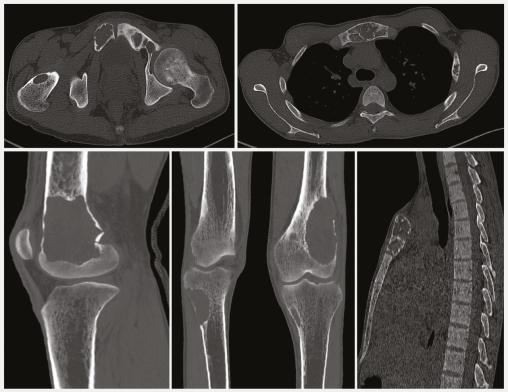

Un scanner cervico-thoraco-abdomino-pelvien (CTAP) réalisé par la suite montre la présence d’une formation rétrothyroïdienne droite, bien limitée, hypodense, se rehaussant après injection de produit de contraste, de 20 mm de grand axe faisant évoquer un adénome parathyroïdien (fig. 1 ). Un deuxième CTAP met en évidence de multiples lésions ostéolytiques du squelette axial et périphérique soufflant et rompant la corticale osseuse par endroits et se rehaussant après injection de produit de contraste, correspondant à des tumeurs brunes (fig. 2 ).

Une radiographie standard des deux genoux en incidences de face et de profil objective des lésions ostéolytiques rompant la corticale osseuse.